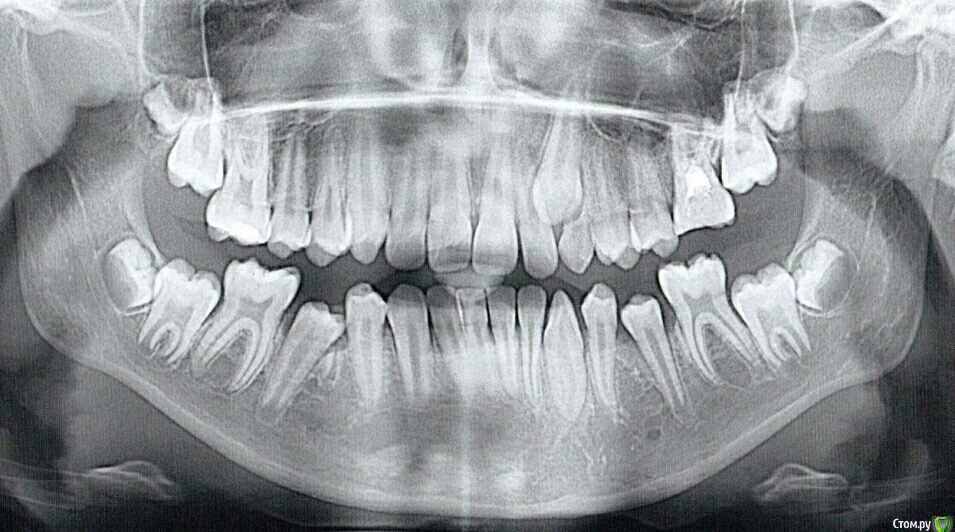

tatty178 Опубликовано 16 января, 2017 Поделиться Опубликовано 16 января, 2017 Здравствуйте. Девочке 11 лет. Молочный зуб стоит, как зацементированный, а клык, видимо, упирается в двойку и выворачивает его, посмотрите на фото. Не могу определиться, что же делать в этом случае. Нахожусь между молотком и наковальней. Очень прошу совета. Высылаю все, что есть. Помогите своим мнением!!! Ссылка на комментарий

krokomot Опубликовано 17 января, 2017 Поделиться Опубликовано 17 января, 2017 Нужно вытягивать ретенированныфй клык, по кт можно определиться с доступом, с удалением молочного зуба думаю проблемм не будет., ну и конечно это фиксация бреккетов, в чем сомнения то? Ссылка на комментарий

tatty178 Опубликовано 17 января, 2017 Автор Поделиться Опубликовано 17 января, 2017 (изменено) Спасибо за ваш ответ. А сомнения у меня по поводу того, нужно ли рвать молочный зуб. Боюсь, а вдруг постоянный зуб так и будет упираться в двойку и не сможет выйти на место вырванного молочного зуба. Такие случаи имеют место быть, о них меня предупредил хирург, который из четырех молочных зубов, вырвал три без тени сомнения, а вот этот все никак не решается. Именно этот зуб стоит, как вкопанный и я боюсь, что дырка так и останется. Наш ортодонт говорит, что этот молочный, как и три предыдущие, нужно удалить. Хирург советует подождать годик, а потом решать. Что же делать? Изменено 17 января, 2017 пользователем tatty178 Ссылка на комментарий

krokomot Опубликовано 17 января, 2017 Поделиться Опубликовано 17 января, 2017 сначала вы удаляете это молочный зуб затем фиксируете бреккет систему, вместе с ортодонтом по диагностическим моделям вы выясните потребуется ли удаление еще других зубов, после создания места для ретенированного клыка проводится обнажение его коронки и фиксация на него кнопки и последующее его вытяжение. В зависимости от фазы роста девочки это вы тоже делаете с ортодонтом, решаете что и когда делать. Лично я ждать бы не стал и сразу обратился к квалифицированному ортодонту. Что вам еще не понятно? Ссылка на комментарий

tatty178 Опубликовано 18 июня, 2017 Автор Поделиться Опубликовано 18 июня, 2017 (изменено) Всем добрый вечер! Вот, что я сделала: удалил хирург нам зуб числа 18 января, а сегодня, спустя пять месяцев, проклюнулся долгожданный клык. Наш ортодонт так и прогнозировала: удаляйте, массажируйте и ждите. Дождались!!!))) Изменено 18 июня, 2017 пользователем tatty178 1 Ссылка на комментарий